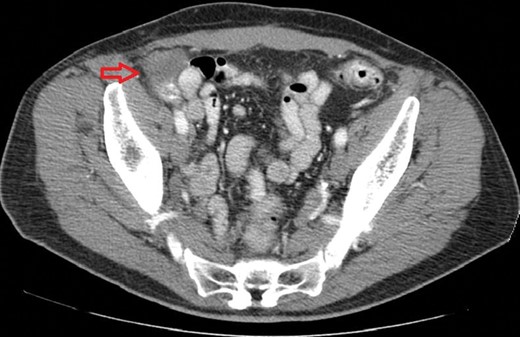

The mass was found in the cecum during routine colonoscopy (Fig. 1); it had raised borders, did not have a stalk and was not associated with mucosal erythema or ulceration. Biopsies showed normal colonic mucosa. A computed tomography (CT) scan of the abdomen showed a 3.3 × 4 cm mass that compressed the wall of the cecum. There was no associated lymphandenopathy or liver lesions (Fig. 2). Based on these findings, we could not conclude if the aforementioned mass was intramural or extramural to the cecum. Due to the uncertainty about the location of this mass (intramural versus extramural) and the inability to rule out a neoplasm, we proceeded with a diagnostic laparoscopy with the possibility of resection of the cecum. Intraoperatively, we found that the right inguinal hernia had been repaired using a plug-and-patch technique. The mesh plug was fixed in the preperitoneal space and had not violated the peritoneal layer. The ‘Plug’ had not fully deployed in the preperitoneal space and had retained a cone-like shape. The wall of the cecum appeared normal and there were no masses in its anterior wall. An intraoperative colonoscopy was done to confirm the absence of a mass; upon insufflation of the colon, it became apparent that the cecal wall was pressed against the non-deployed plug thereby creating the impression of a mass with extrinsic compression.

CT scan of the abdomen with intravenous and oral contrast demonstrating a mass in the right lower quadrant adjacent to the cecum.